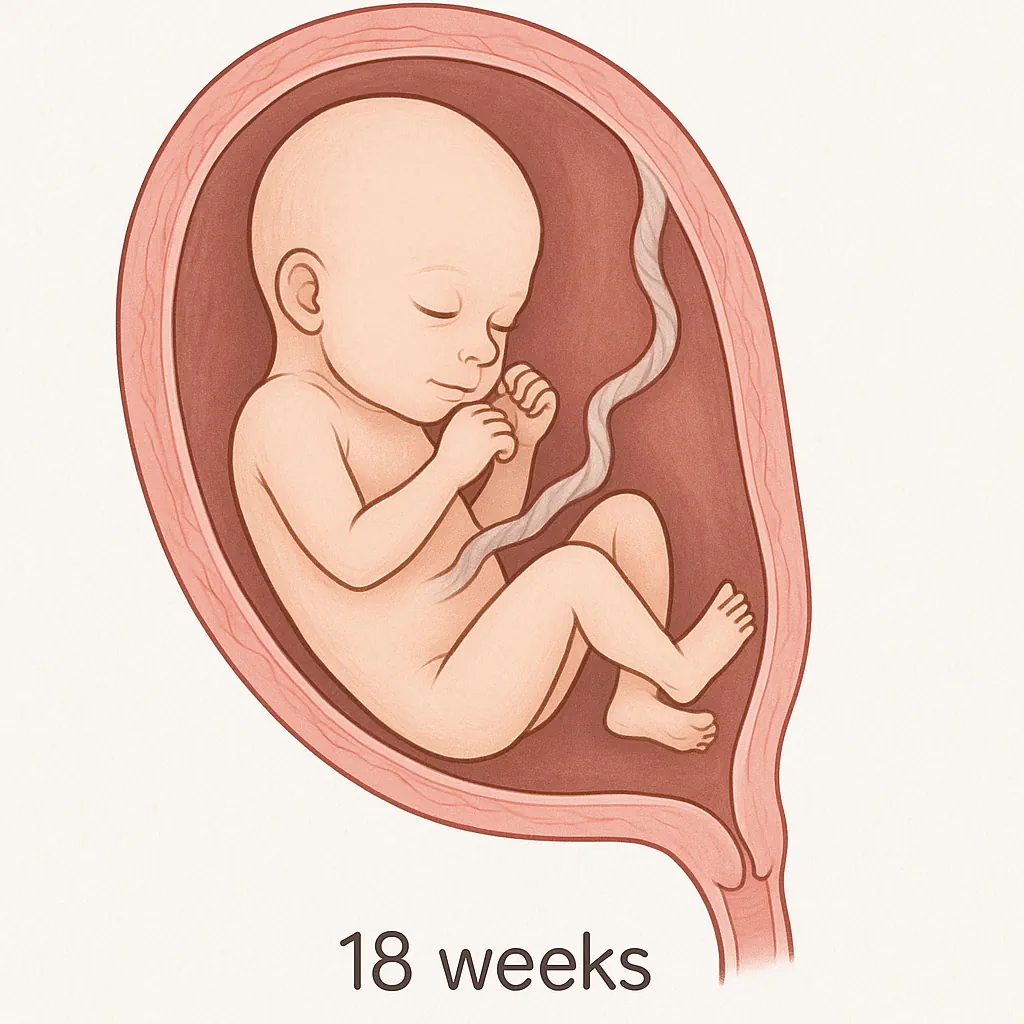

در هفته هجدهم بارداری، شما وارد یکی از هیجانانگیزترین مراحل بارداری خود میشوید؛ زمانی که ممکن است حرکتهای کوچک و واقعی جنینتان را برای نخستینبار حس کنید. در این هفته، کودک شما حدود ۱۴.۲ سانتیمتر طول دارد؛ تقریباً به اندازهی یک فلفل دلمهای کوچک!

رشد و شکل جنین در هفته هجدهم بارداری (جنین ۱۸ هفته چه شکلی است؟)

اگر در هفته هجدهم بارداری سونوگرافی انجام دهید، احتمالاً جنین خود را در حال مکیدن انگشت شستش خواهید دید؛ حتی ممکن است با چهرهای اخمو یا کنجکاو شما را نگاه کند، انگار میگوید: «باز هم آمدی؟».

در این مرحله، چهرهی جنین ۱۸ هفته بهتدریج واقعیتر میشود و استخوانهای صورت و بدن او در حال محکم شدن هستند.

اثر انگشتهای مخصوص او تقریباً تشکیل شدهاند و قلبش اکنون بهطور کامل شکل گرفته است. هنگام سونوگرافی، میتوانید ساختار قلب، کبد، و استخوانها را بهوضوح ببینید.

حواس جنین نیز با سرعت زیادی در حال رشدند؛ او اکنون پرزهای چشایی زیادی روی زبان خود دارد و قدرت شنواییاش فعال شده است.

مسیر بین استخوانهای گوش میانی تا مغز شکل گرفته و او میتواند صداهایی مانند ضربان قلب، جریان خون و حرکت بند ناف را بشنود. حتی گاهی ممکن است از صداهای بلند بترسد یا واکنش نشان دهد.

در صورتی که نور شدیدی به شکم شما بتابد، جنین در هفته ۱۸ بارداری میتواند تفاوت روشنایی را احساس کند.

ارگانهای داخلی مانند کبد و قلب او در حال رشد سریع هستند و برای جای گرفتن بهتر، بدنش حالت صافتر و کشیدهتری به خود میگیرد.

تا این مرحله، بدن او شامل حدود ۲۰۰ استخوان است که برخی در ادامه به هم جوش میخورند تا در نهایت، اسکلت انسان بالغ با ۲۰۶ استخوان شکل بگیرد.

در این هفته، اندازه جنین تقریباً برابر با جفت اوست. جفت همچنان منبع اصلی دریافت غذا و اکسیژن و همچنین خروج مواد زاید است.

هفته ۱۸ بارداری در واقع پایان ماه چهارم بارداری و آغاز ماه پنجم است. در این مرحله جنین حدود ۲۰۰ گرم وزن و ۱۴ سانتیمتر طول دارد.

🟣 وزن و اندازهی جنین در هفته ۱۸ بارداری چقدر است؟

در این هفته جنین حدود ۲۰۰ گرم وزن و ۱۴ تا ۱۴.۵ سانتیمتر طول دارد، تقریباً به اندازهی یک فلفل دلمهای کوچک.